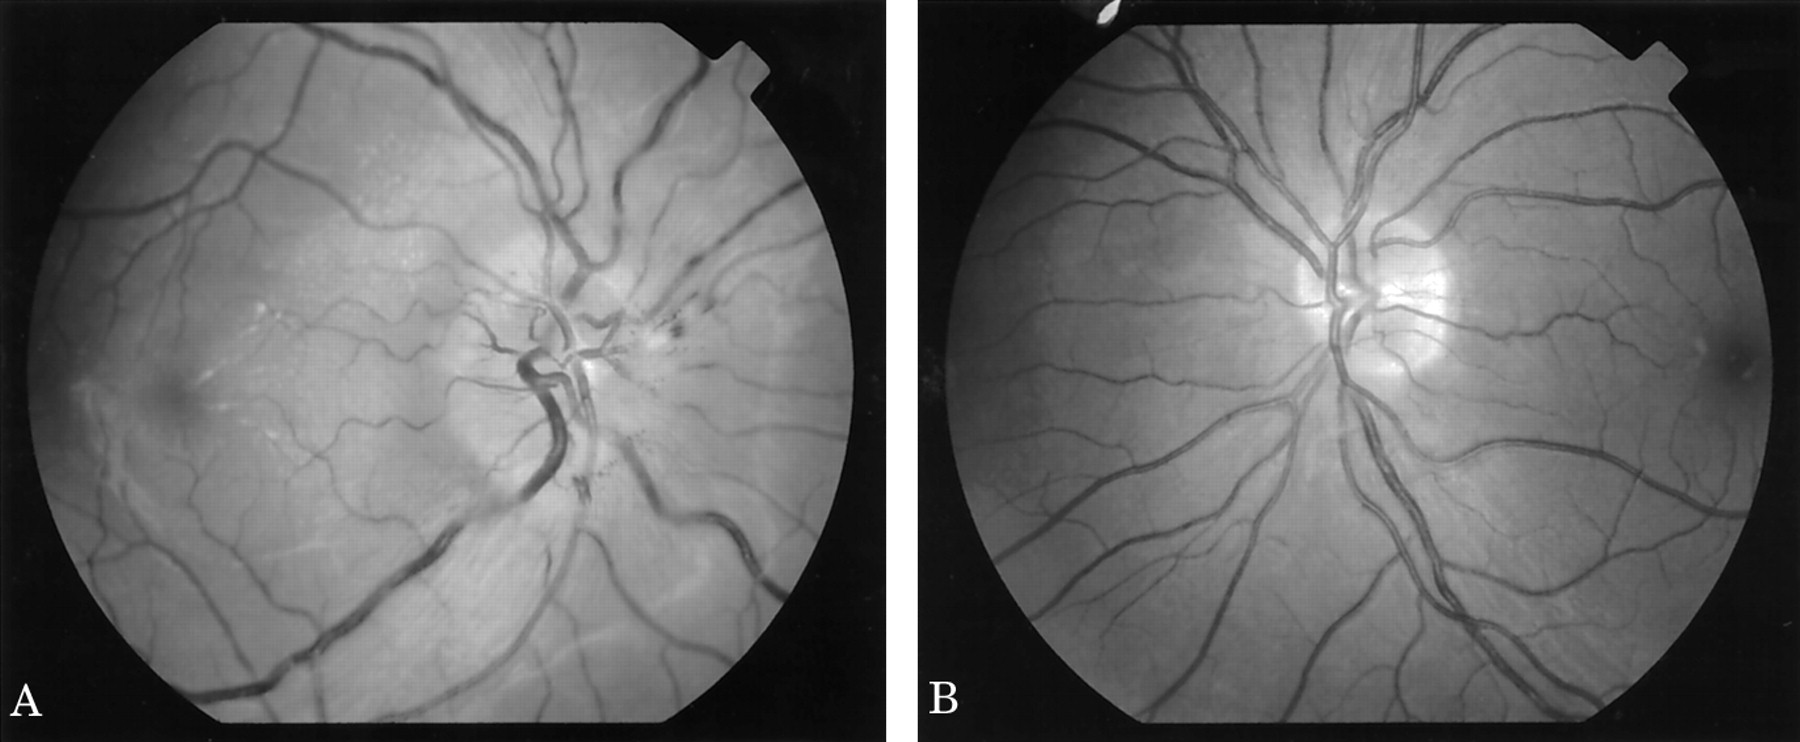

在影响视力范围从20/20到20/100,20/20到20/30的未受影响的眼睛。色觉是正常的14个病人。例15有20/100的视力影响眼睛黄斑水肿造成的,也是唯一的病人减少颜色视觉。视野测试表明只有一个扩大盲点8 15例。四个还不如鼻抑郁,和三个一般的收缩。视野异常都是单方面的,受影响的眼睛。正常的裂隙灯活组织镜检查和对称的眼内压力被发现除了一个病人(病人4)。8检眼镜检查受影响的眼睛显示单侧视神经盘水肿(图1)。视网膜视神经盘旁出血被认为在四个病人,二级脉络膜的折叠在两个病人,病人和黄斑水肿。检眼镜检查未受影响的眼睛显示没有异常的视神经盘或视网膜。